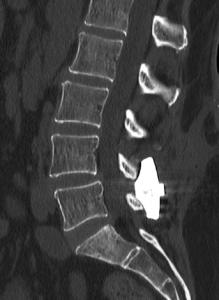

INSPAN, LLC is privately owned by the KICVentures Group and is focused on advancing the platform of patented interspinous fixation technology. The Inspan device has a proven ten-year track record with thousands implanted since FDA clearance in 2010. https://myinspan.com/

Inspan Sawbone Demonstration by Prof. Dr. Kingsley R. Chin